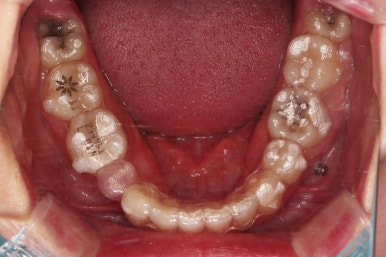

장치 부착 직후의 모습인데요.

장치가 어디있냐고요?

이번 환자분이 선택하신 장치는 인비절라인이라는 투명교정장치였기 때문에 치아에는 유심히 관찰해 보면 보이는 작은 치아색깔의 어태치먼트라는 버튼 이외에는 부착물이 없답니다.

저 상태로 투명교정장치를 빼고 끼면서 치아를 움직이게 됩니다.

필요한 발치, 급한 충치치료는 마무리된 상태이고요.